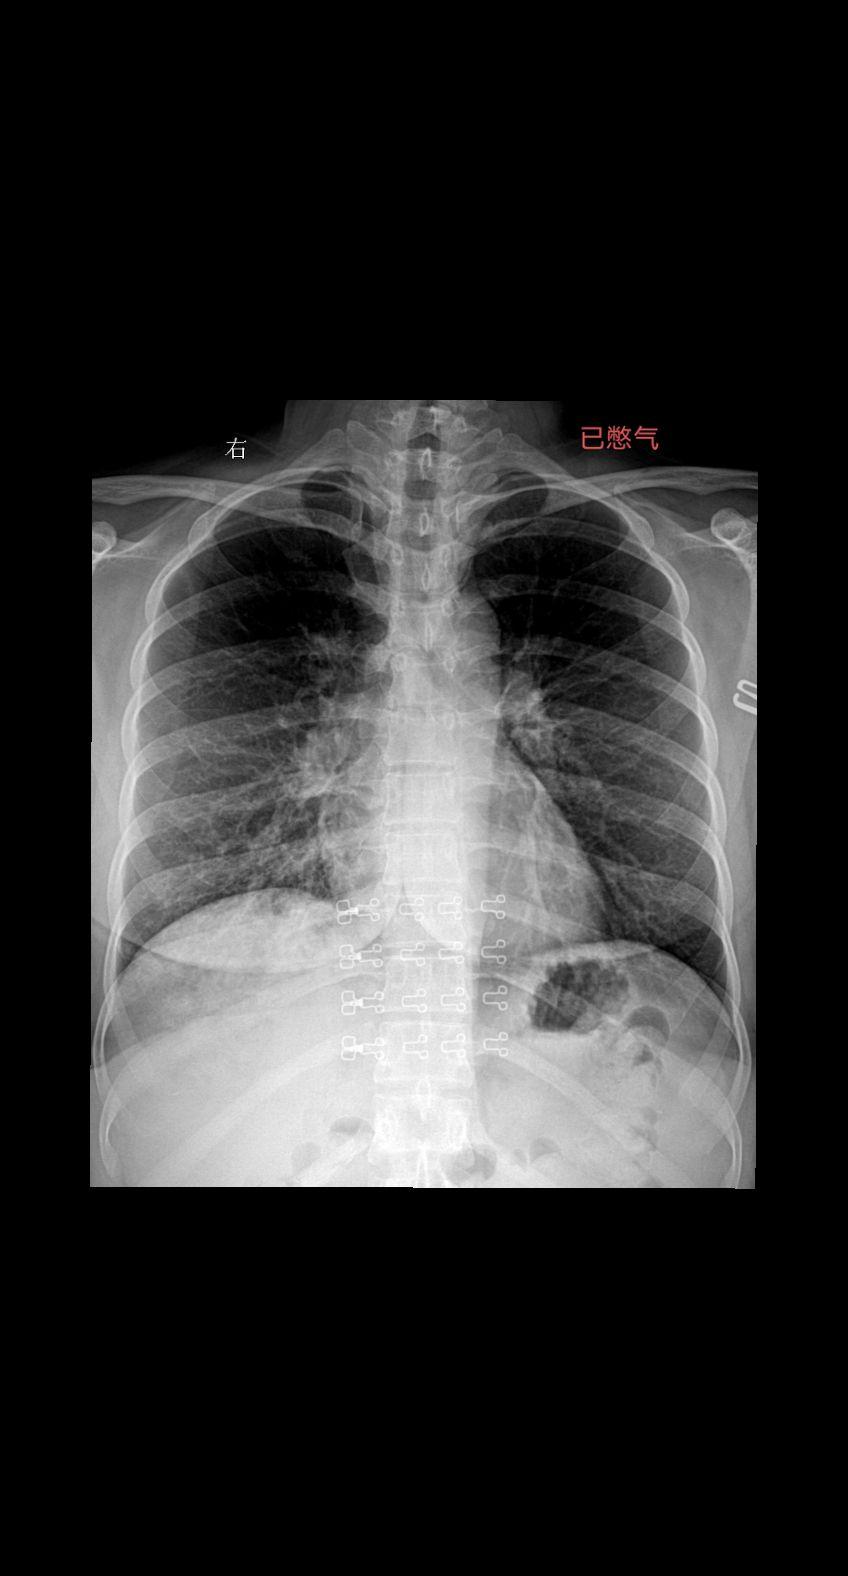

家人们你们拍胸片的时候让患者深呼吸憋气吗 患者主诉咳嗽感冒一周29岁女